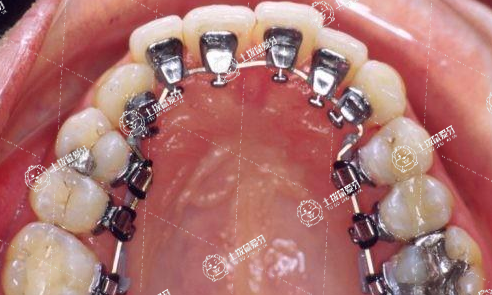

舌側(cè)矯正就是在牙齒的內(nèi)側(cè)也就是舌側(cè)安裝托槽的一種矯治方法,對醫(yī)生的技術(shù)水平要求很高,還能減少拔牙率,在旁人看不出來的情況下矯治了牙齒,又完全不影響美觀。

舌側(cè)矯正

舌側(cè)隱形矯正在經(jīng)過多年的理論體系的研究還有對矯正技術(shù)不斷的完善,目前已經(jīng)矯正效果已經(jīng)變得十分良好,對于絕大多數(shù)的患者的牙齒都能有很好的矯正效果,而且舌側(cè)隱形矯正有隱形的效果,也不會對人體口腔的內(nèi)側(cè)唇部有損傷作用,可有效的矯正牙齒不整齊的癥狀,在矯正6~12個月左右就可以達到比較明顯的效果,然而要選擇去正規(guī)的醫(yī)院進行矯正,正規(guī)醫(yī)院的醫(yī)生可以針對個人的實際情況給予適合的矯正方案,這樣矯正的效果才會更理想。